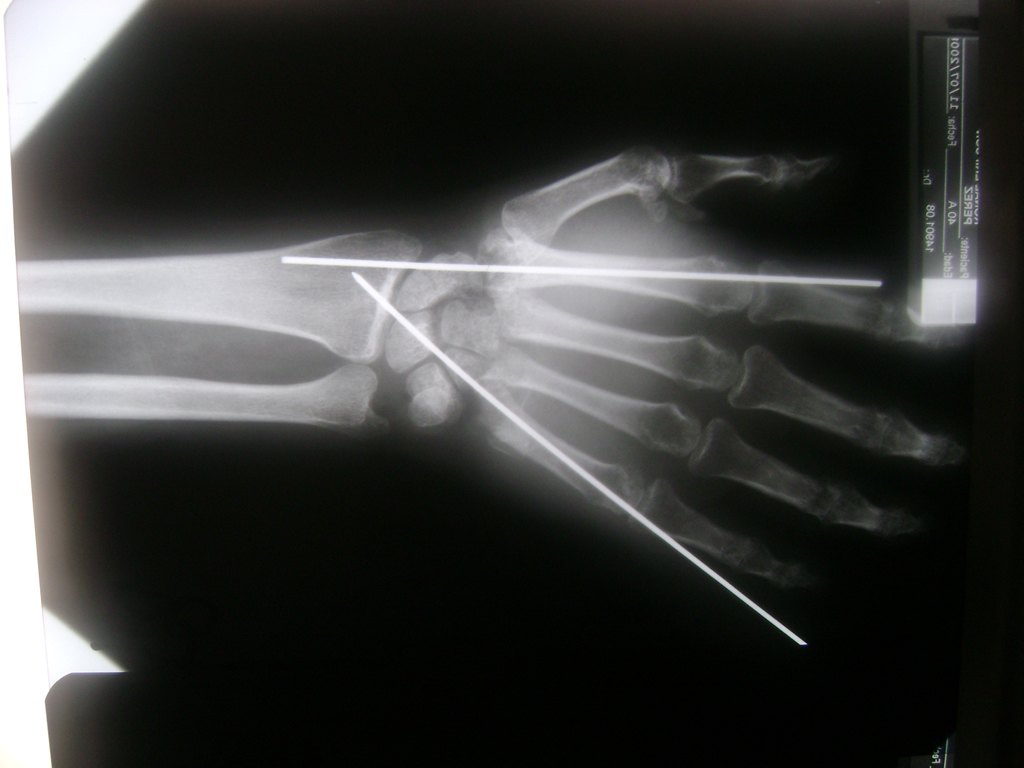

Cirugías de Codos - Cirugías de Muñecas y Manos

Los procedimientos más comunes en cirugía de la mano son aquellos destinados a reparar traumatismos, incluyendo lesiones de tendones, nervios, vasos sanguíneos, y articulaciones; huesos fracturados; y quemaduras, cortes, y otros daños de la piel.